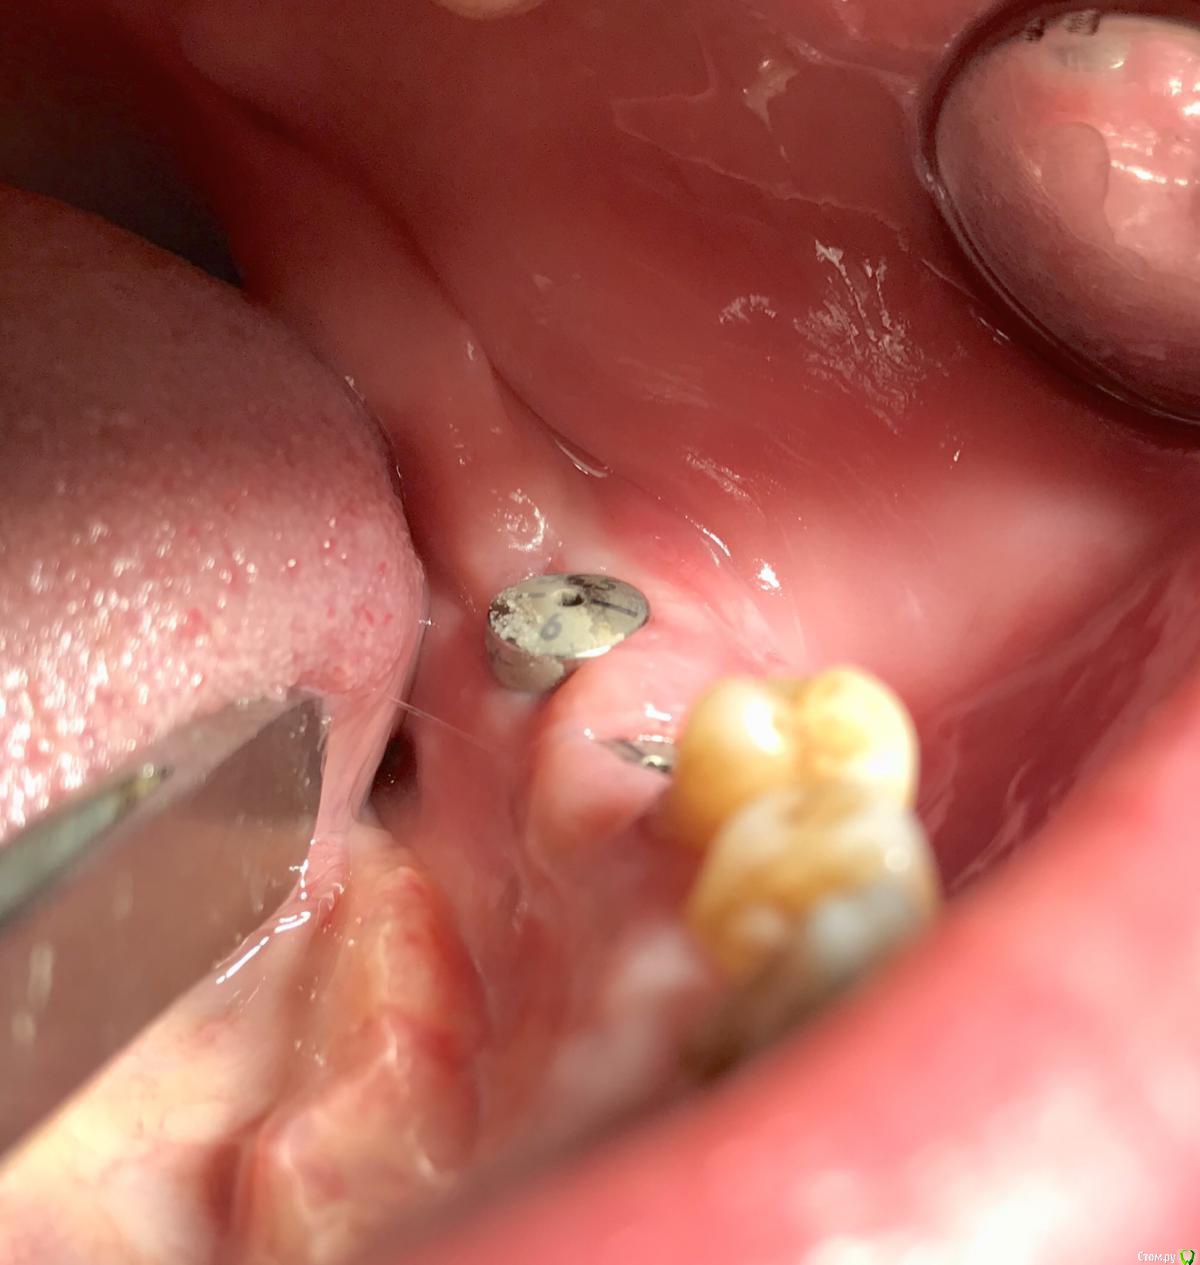

колесников Опубликовано 22 декабря, 2018 Автор Поделиться Опубликовано 22 декабря, 2018 Контроль просили. 1 пациент. Снимок майский,на тот момент 6-7 мес после вмешательства. Графтинг в обл имплантов и в промежутках ,3,4ый сектор 1 Ссылка на комментарий

колесников Опубликовано 16 февраля, 2019 Автор Поделиться Опубликовано 16 февраля, 2019 Спрашивали кт . Вид через 3-4 мес 1 Ссылка на комментарий

колесников Опубликовано 6 марта, 2019 Автор Поделиться Опубликовано 6 марта, 2019 Продолжение. За прошедшее время произведён асл,замена формирователей на 6ки. Периотест (-6) Ссылка на комментарий

колесников Опубликовано 13 марта, 2019 Автор Поделиться Опубликовано 13 марта, 2019 Ну чтож, прошло 3 месяца,самое время посмотреть что там на кт. 1 Ссылка на комментарий